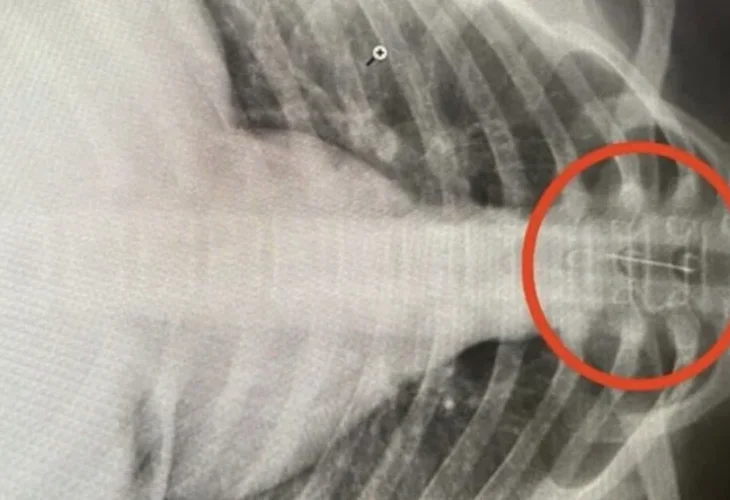

ד"ר אילשאט ריסקוז'ין סיפר על המקרה. לדבריו, הנערה סבלה מכאבים עזים בחזה, התקשתה לנשום, השתעלה וסבלה מריור בלתי נשלט. בבדיקת הרנטגן שעברה התגלתה המחט בקנה הנשימה שלה: "ראינו שמדובר במחט קטנה שעושה שמות בגופה. מיד יצרנו קשר עם מומחים, והחלטנו להעביר אותה לניתוח דחוף בבית החולים בעיר אופה".